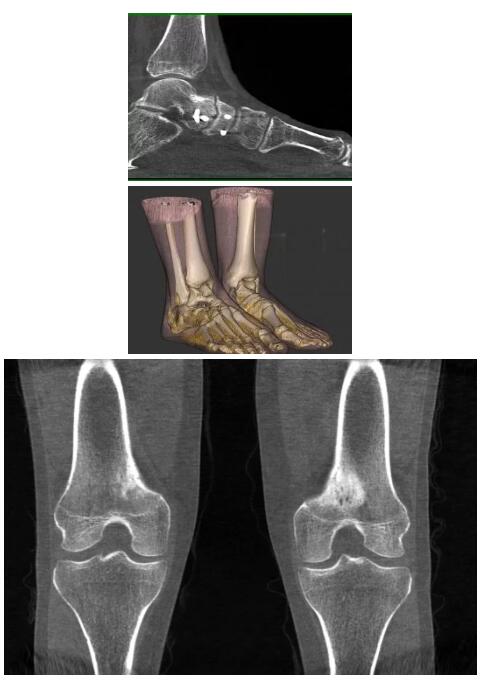

而患者站著做足部或者踝部做CT檢查還有個好處是,可以檢查患者在負(fù)重的情況下,骨關(guān)節(jié)的真實(shí)情況,而躺著做CT掃查時未必能看出來。負(fù)重CT掃查特別是對于受傷的運(yùn)動員或者舞蹈員來說意義更大,能夠更準(zhǔn)確地評估傷情,幫助他們盡早復(fù)原。

以上介紹的CT均來自國外同一家公司,這些CT均配置了可視化軟件,可以進(jìn)行切片、3D重建以及大型CT附帶的所有典型的操作功能。

以下是這些“特立獨(dú)行”的CT所拍出來的圖像: